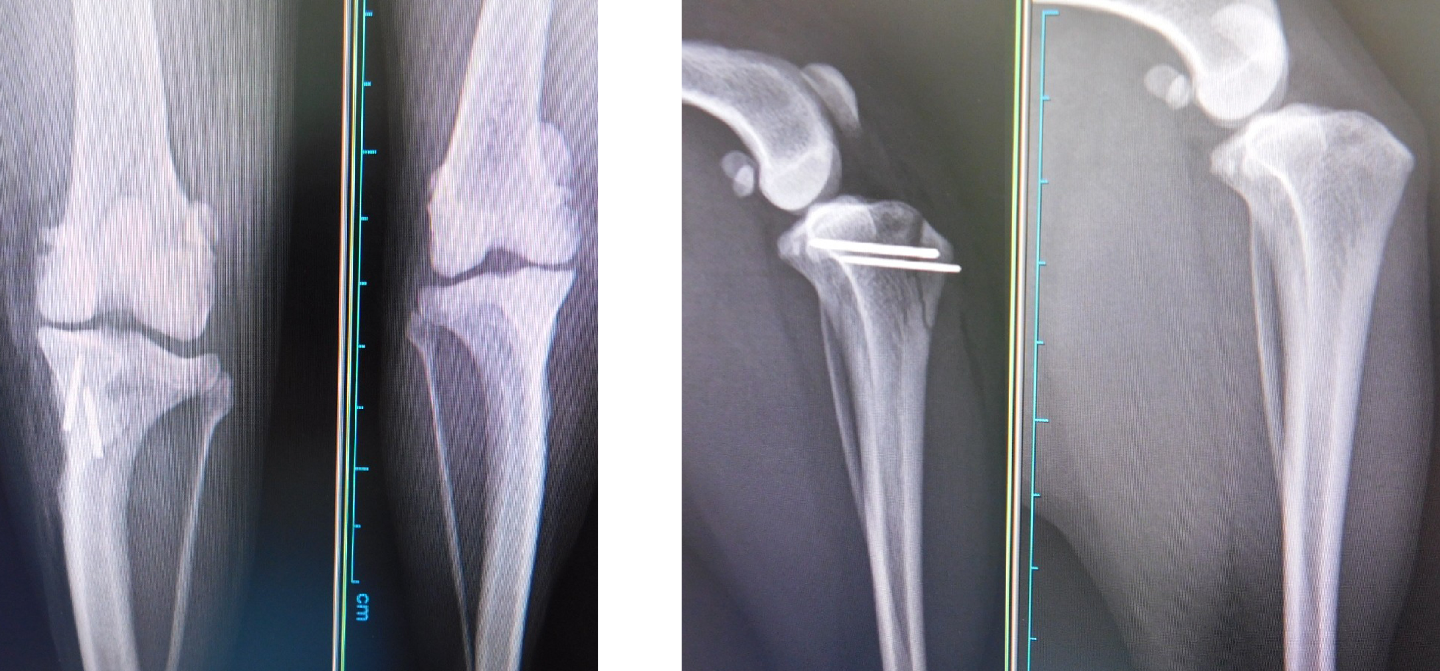

②脛骨粗面外側転移

パテラの靱帯付着部である脛骨粗面が内側に曲がっているので骨切りをして正中に整復してピンで固定します。

成長期で脛骨粗面が閉じていない場合は吸収糸で外側に引っ張り脛骨を内旋しないようにします。